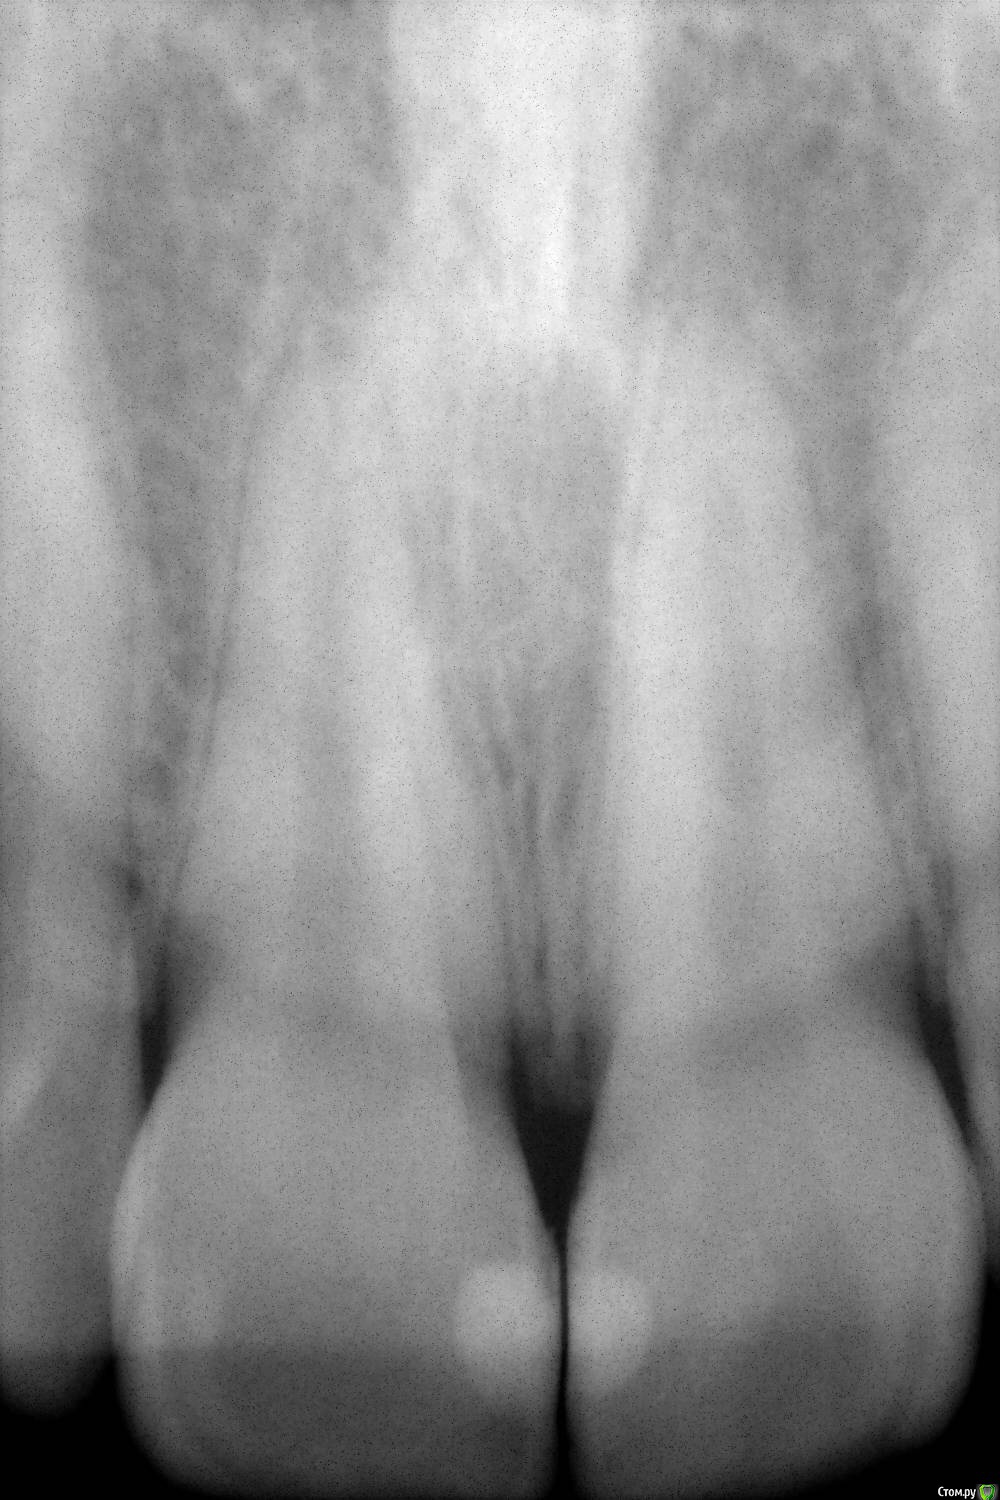

Evgen-Vozhd Опубликовано 14 марта, 2017 Поделиться Опубликовано 14 марта, 2017 (изменено) Пациентка 20 лет, никакой симптоматики нет, кроме эстетического эффекта. Появляется самопроизвольно и так же без всякого лечения проходит через 3-7 дней. Гигиена хорошая, поддесневого зубного камня нет. С виду похоже на точечные кровоизлияния. Что за Чуда-юда?Извиняюсь, тема наверное больше для терапевтического раздела. не знаю как перенести Изменено 14 марта, 2017 пользователем Evgen-Vozhd Ссылка на комментарий

anvladd Опубликовано 14 марта, 2017 Поделиться Опубликовано 14 марта, 2017 Снимки Ссылка на комментарий

Evgen-Vozhd Опубликовано 14 марта, 2017 Автор Поделиться Опубликовано 14 марта, 2017 Ссылка на комментарий

Evgen-Vozhd Опубликовано 16 марта, 2017 Автор Поделиться Опубликовано 16 марта, 2017 Вряд ли это травма... не выглядит как раневая поверхность. точечные каппилярные гематомы, при надавливании не исчезает. боли нет, появляется и исчезает бессимптомно...хз.. Ссылка на комментарий